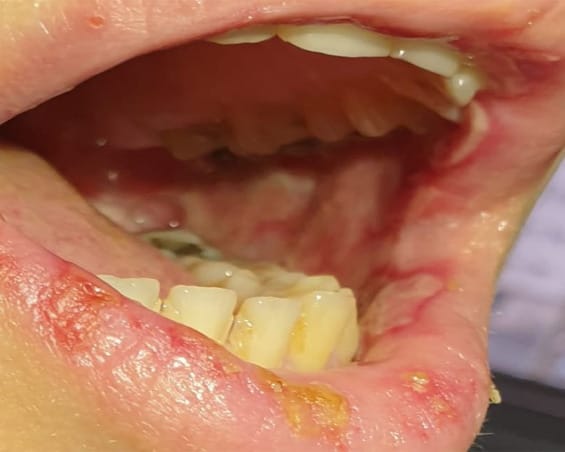

A middle-aged female patient came to the College of Dentistry, Taibah University, Saudi Arabia, 5 days after the second dose of the COVID-19 Pfizer vaccine, complaining of large, red-colored bullae at the left retromolar area (Figure 1) that ruptured and refilled.

Fig. 1 Large, deep-red bullae at retromolar area. Fig. 2 Large oral ulcerations at labial mucosa with yellow crust at lower lip. Fig. 3 Multiple large oral ulcerations at buccal mucosa.

The patient reported that she had taken the second dose of the BNT162b1 SARS-CoV-2 vaccine 5 days previously. The patient reported that she had a mild fever and general weakness. A D-dimer test was done to detect the possibility of blood clots. Laboratory examination of the D-dimer test showed a slight elevation with 0.63 mg/L.